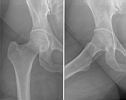

Heup